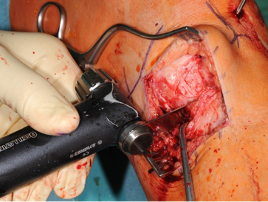

Access with preparation of an anterior pedicled periosteal flap for subsequent covering of the osteotomy gap

We usually do not use a tourniquet for osteotomy. The skin incision is a medial longitudinal incision, especially with a view to any subsequent revision surgery with knee replacement or if an arthrotomy for a cartilage procedure is required in the same session. Alternatively, an oblique incision can be made at the level of the pes anserinus.

Now the superior margin of the pes anserinus is exposed, then the anterior portion of the superficial medial collateral ligament and the tuberosity. We prepare (with the knife) a periosteal flap from the lateral side at the anterior margin of the medial collateral ligament, and superior margin of the pes anserinus up to the tuberosity. This periosteal flap is pedicled to the tuberosity and by incising it on the cranial portion it can be pivoted and be used to mostly cover the osteotomy site after the plate fixation (Fig. 3).